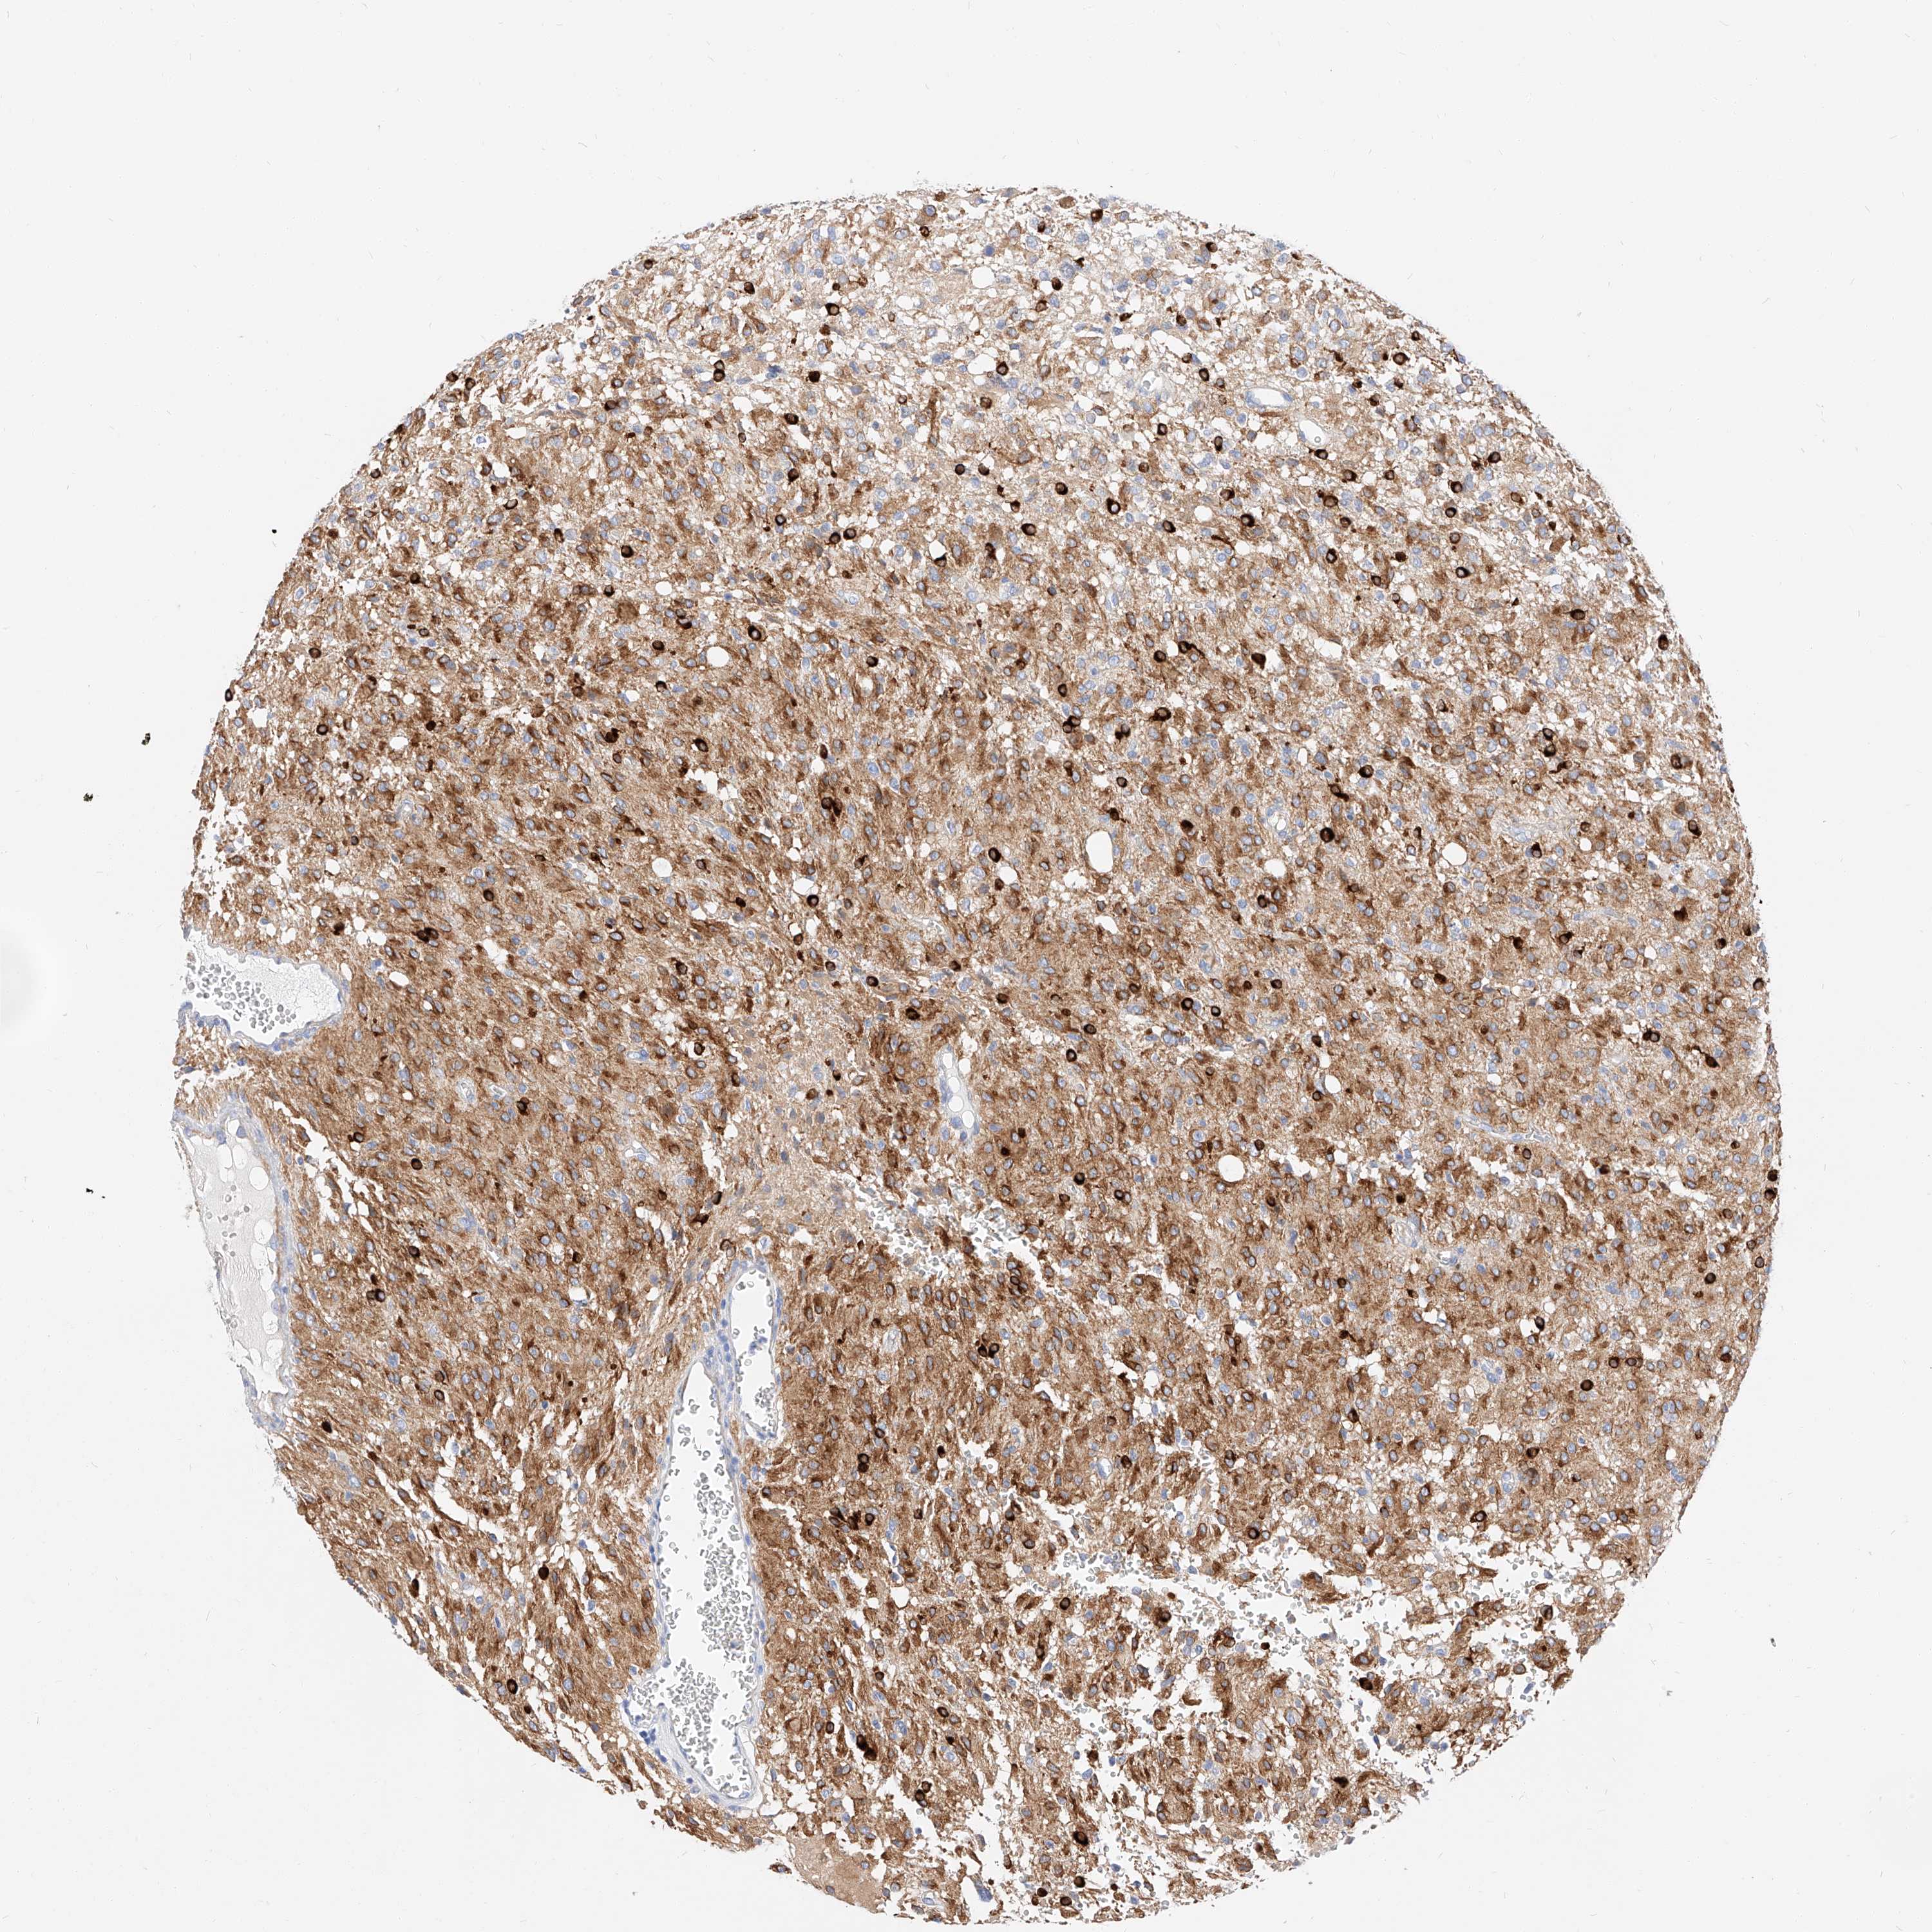

GLIOMA - Protein expressioni

A mouse-over function shows sample information and annotation data. Click on an image to view it in a full screen mode. Samples can be filtered based on level of antibody staining by selecting one or several of the following categories: high, medium, low and not detected. The assay and annotation is described here.

Note that samples used for immunohistochemistry by the Human Protein Atlas do not correspond to samples in the TCGA dataset.

Antibody stainingi

Antibody staining in the annotated cell types in the current human tissue is reported as not detected, low, medium, or high, based on conventional immunohistochemistry profiling in selected tissues. This score is based on the combination of the staining intensity and fraction of stained cells.

Each image is clickable and will lead to virtual microscopy that enables deeper exploration of all samples and also displays staining intensity scores, fraction scores and subcellular localization as well as patient and tissue information for each sample.

Antibody HPA029712

Antibody HPA029713

Staining

High

Medium

Low

Not detected

Intensity

Strong

Moderate

Weak

Negative

Quantity

>75%

75%-25%

<25%

None

Location

Nuclear

Cytoplasmic/membranous

Cytoplasmic/membranous,nuclear

Glioma, malignant, High grade

Glioma, malignant, Low grade

Glioblastoma, NOS